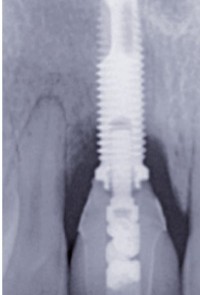

Article réservé à nos abonnés Prophylaxie implanto-prothétique : la part du patient

Selon Lee et coll. [1], la prévalence de la péri-implantite est décrite comme touchant plus de 9 % des implants posés,...